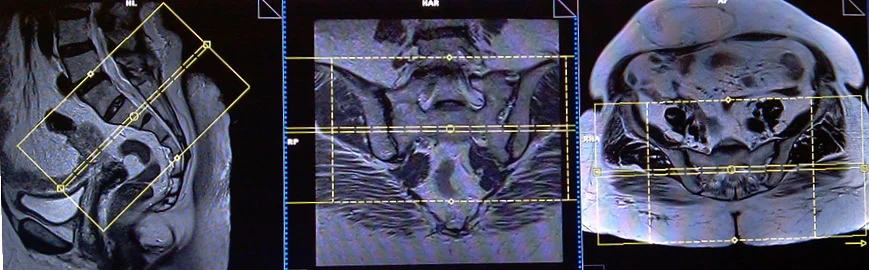

CASE STUDY NO.2

Coronal planning

Axial planning